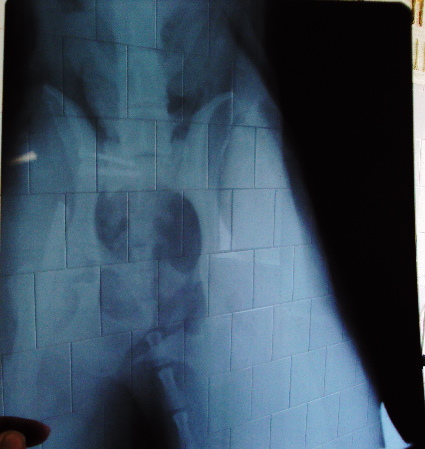

Бела преди приемането в клиниката.

Първите две операции платихме ние, а третата я направиха благотворително от клиниката. Засега се справяме с парите. Ако всичко мине благополучно й предстоят още три операции за изваждане на железата, но... нека да стигнем до там!

Това са снимки на Бела от вторник, вчера нямах сили да я снимам, станала е кожа и кости... Много ми е мъчно!